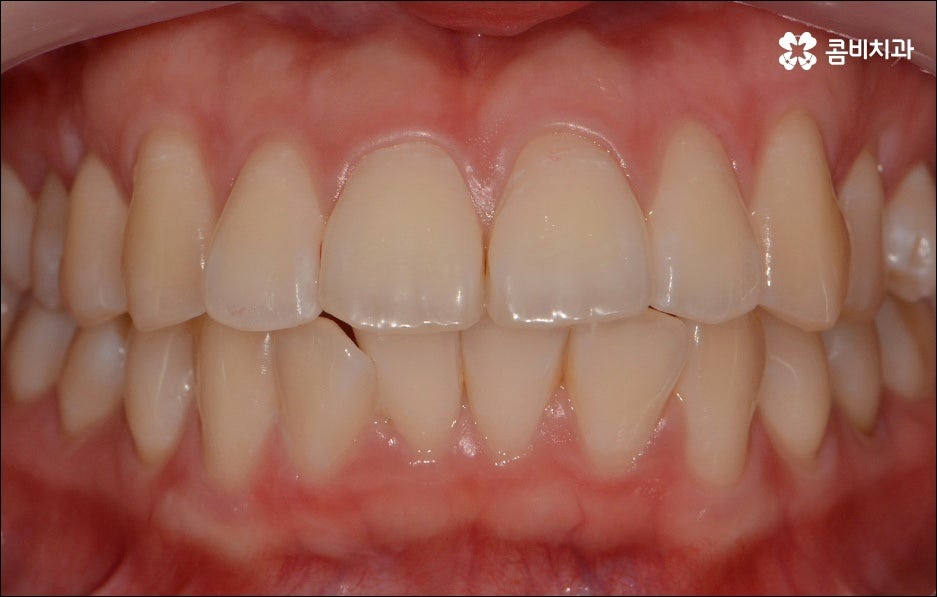

치열이 불규칙하여 기능적 심미적인 불편을 겪는 분들 중에 교정 치료를 고민하시는 분들이 많이 있습니다. 특히 앞니는 다른 치아보다 훨씬 외부에 잘 드러나므로 대화하거나 웃을 때 만약 앞니 사이가 벌어져 있거나 앞니 돌출 이 된 경우, 비틀어진 경우에는 신경이 많이 쓰일 수 있는데요. 하지만 막상 교정을 시작 하려고 하면 기간이 오래 걸리는 것 때문에 또는 치료 과정 자체에 부담을 느껴서 망설이시는 분들도 있을 수 있어요. 이때 앞니 외 다른 치아 배열 또는 위아래 교합에는 별다른 이상이 없다면 문제가 있는 앞니만 부분교정으로 치료할 수 있으니 이에 대해서 한 번 알아보시면 도움이 되실 거예요.

부분교정은 짧은 기간에 모든 치아가 아닌 특정 치아만 집중적으로 교정하는 것으로, 예를 들어 앞니 돌출 을 개선하기 위해 앞니와 그 옆의 치아까지 6~8개의 치아에만 브라켓을 장착하여 교정 치료를 하는 것을 의미하고 있어요. 비교적 간단한 과정이라고 생각하실 수 있으나 다른 치아에는 영향을 주지 않으면서 주변 치아와 앞니의 이동량을 고려하여 교합을 세밀하게 조정하고 전체 균형을 맞춰나가야 하는 만큼 의료진의 높은 숙련도가 필요한 과정이라고 할 수 있는데요.

상황에 따라 다르지만 전체 교정이 통상적으로 1년에서 2년 반 정도의 기간이 걸리는 데 반해서 앞니 돌출 부분교정은 3~6개월 정도의 짧은 기간이 소요되며 발치에 대한 걱정이나 비용에 대한 부담도 줄여주기 때문에 많은 분들이 가능하다면 부분 교정 치료를 받고 싶으실 수 있어요. 하지만 누구나 부분 교정 치료가 가능한 것은 아니며 앞니 돌출 원인과 현상에 대한 꼼꼼한 분석을 통해 가능한지 여부, 치료 시기, 방법 등이 모두 달라지기 때문에 먼저 정확한 검진 및 충분한 상담부터 진행해 보시는 것을 추천드리고 있습니다. 또한 환자 개개인의 상황을 정확하게 검진하고 맞춤 플랜을 세울 수 있는 정밀 장비와 꼼꼼한 사후관리 시스템을 갖추고 있는 치과에서 무리하지 않게 치료 받는 게 중요하다는 점을 명심하시길 바라고 있어요.